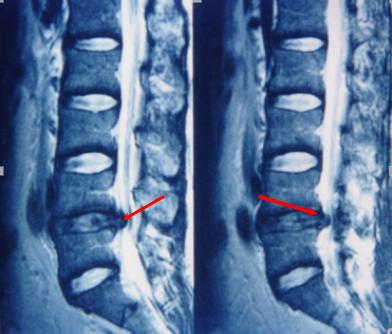

磁共振检查:跟CT一样,具有确诊价值,同时由于其成像原理,对于观察神经以及是否存在神经压迫水肿信号,有独特的优势,也是目前诊断腰椎间盘突出,明确神经压迫的主要检查,老百姓没学过医的也可以看得到的“突出”!

症状是典型的腰腿痛症状,还伴有麻木(灯泡一闪一闪了)神经异常放电,当时还没有学医的我去了家里的镇医院做了一个磁共振检查,当时拿到黑胶片的时候,连一个刚成年的我都看到了我那明显突出的“椎间盘”,白白的亮闪闪的......